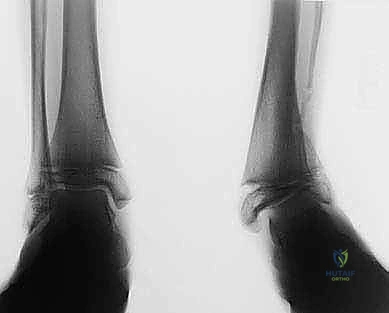

الحالة الأولى: تصحيح تشوه ما بعد كسر قديم

مريض يبلغ من العمر 42 عاماً، تعرض لكسر في الساق قبل 5 سنوات التئم بشكل خاطئ، مما أدى إلى تقوس شديد للداخل (Varus) وألم مستمر يمنعه من العمل. بعد تقييم دقيق من قبل الأستاذ الدكتور محمد هطيف، تم إجراء جراحة قطع عظم الساق فوق الكاحل بتقنية الوتد المفتوح. بعد 4 أشهر من الجراحة والتأهيل، عاد المريض لعمله الميداني بمحور ساق مستقيم تماماً وبدون أي ألم.

الحالة الثانية: إنقاذ كاحل شابة من الخشونة المبكرة

شابة تبلغ من العمر 28 عاماً، تعاني من تشوه خلقي أدى إلى تركز الوزن على الجانب الخارجي للكاحل، وبدايات تآكل غضروفي. كانت مهددة بدمج الكاحل في سن مبكرة. أجرى لها الدكتور هطيف الجراحة ببراعة، مما أعاد توزيع الوزن بشكل مثالي، وأنقذ مفصلها الطبيعي، وعادت لممارسة حياتها الطبيعية بثقة عالية.

الأشعة السينية بعد التثبيت النهائي